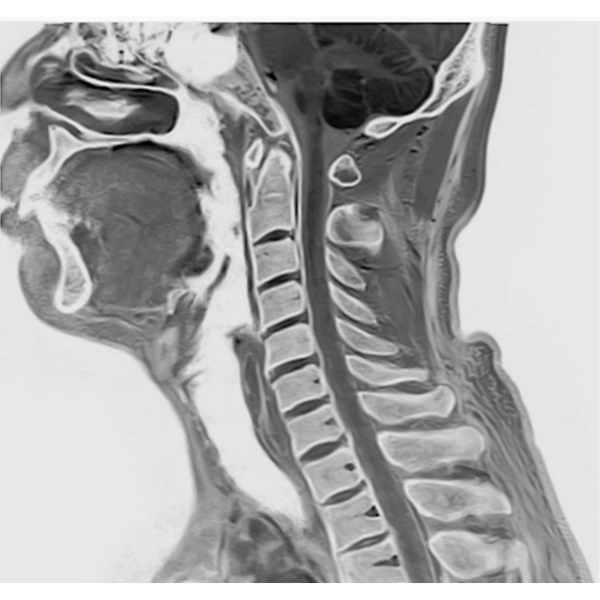

IP-RAPID x DLR Plus can be used for basic imaging such as VolumeScan, RadialScan, HalfScan, and many other imaging methods such as MultiContrastScan FatSep and DWI.

It can also be used with time-consuming scans such as Whole Body DWI and Whole Spine imaging, providing more detailed information in many areas than previously possible.